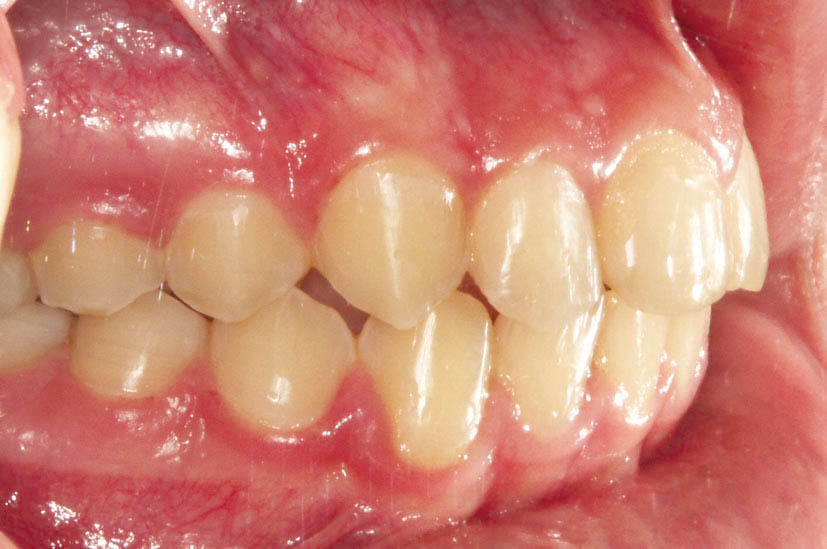

شکل 108-2: قرار دادن مینی اسکرو در یک کاسپ کامل کلاسII

شکل 109-2: نتیجه درمان یک کاسپ کامل کلاسII تمام میشود